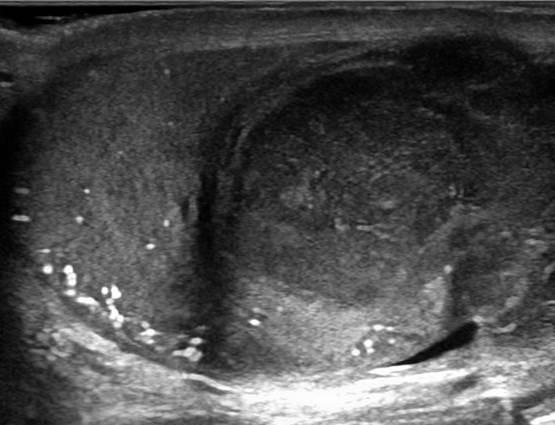

U tinh hoàn

» Thông tin: Nam giới – 28 tuổi.

» Lâm sàng: Sưng tinh hoàn.

# U tinh bào (Seminoma).